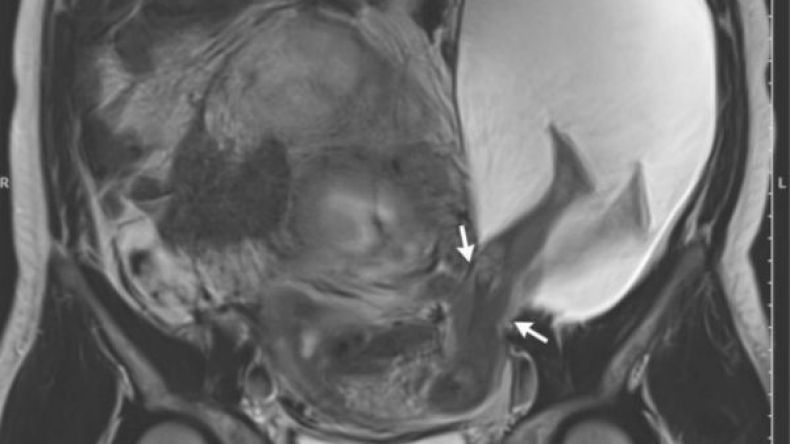

وفحص أطباء المرأة الجنين باستخدام تصوير الرنين المغناطيسي. نشر بويه وزميله صورة للأمنوسيل في دورية New England   الطبية يوم الخميس. وعلى الرغم مما يبدو عليه الأمر، فإن ركلة وحشية من الجنين ليست هي السبب.

يقول بويه، “رجلي الجنين لم تتسبب في الفتق”. عوضاً عن ذلك، يُحتمل أن تكون الولادات القيصرية الخمسة التي أجرتها المرأة سابقاً قد أدت إلى التمزق، في رأي طبيب الولادة. بسبب الندوب من الولادات السابقة، فإن أجزاءً من الرحم بقيت متيبّسة بشكلٍ غير عادي بدلاً من التضخّم في الحجم خلال حملها الأخير. تمزّق جدار الرحم عندما لم يعد قادراً على التمدد، متسبباً في تمزُقٍ بطول بوصة (الصورة بالأعلى، موضحٌ عليها التمزق بالأسهم).